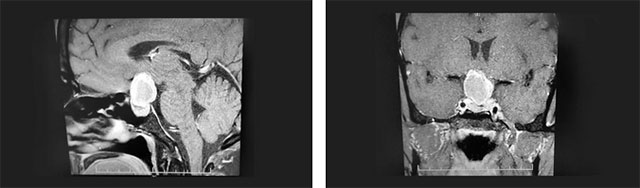

頭顱鞍區(qū)MRI平掃+增強顯示:鞍區(qū)見團塊狀異常信號影,大小約2.6*2.1*2.5cm。瘤灶向上突入鞍上池、第三腦室受壓,鞍隔受壓下塌,垂體上緣受壓變扁。鞍底骨質(zhì)略下陷,視交叉上抬、分界不清。

▲ 術(shù)前影像:垂體大腺瘤,向鞍上生長